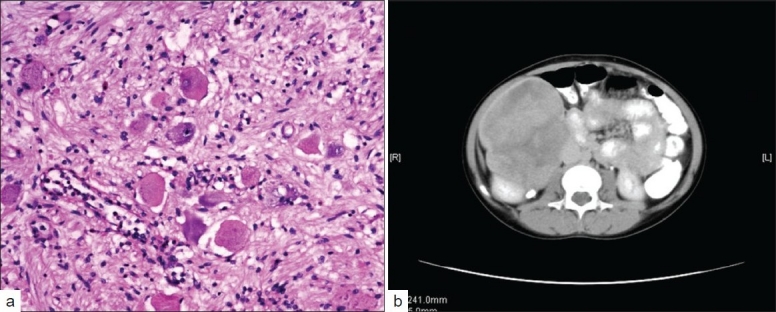

Laboratory investigations revealed a normal hemogram, renal, and liver functions. She had normal 24-hour urine vanillylmandelic acid (VMA) levels and bilateral bone marrow studies. Furthermore, she was investigated with a CT scan of the abdomen [Figure 1a], which showed a large, heterogeneously enhancing mass lesion, arising from the interpolar region of the right kidney extending up to the under surface of the liver superiorly and medially, up to the IVC and laterally up to the abdominal wall. The mass was encasing the renal vessels, but patency was maintained. Nodes were not demonstrable.

| Figure 1 (a) Spindle shaped cells intermixed with mature ganglion cells (b) A large heterogenously enhancing mass apparently arising from the interpolar region of the right kidney extending towards the lower poleShe was taken up for laporatomy. Intraoperative findings revealed a retroperitoneal mass with nodular projections, densely adherent to the anterior surface of the right kidney, encasing the right renal vessels and extending to the IVC. The mass was carefully and completely dissected out with a 2.5 cm portion of the IVC, which was repaired. The histopathological examination was suggestive of GN [Figure 1b].

| Figure 1 (a) Spindle shaped cells intermixed with mature ganglion cells (b) A large heterogenously enhancing mass apparently arising from the interpolar region of the right kidney extending towards the lower pole